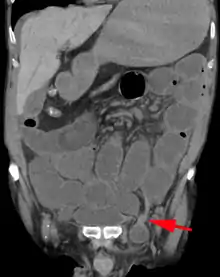

.jpg.webp)

An indirect inguinal hernia results from the failure of embryonic closure of the deep inguinal ring. In the male it can occur after the testicle has passed through the deep inguinal ring. It is the most common cause of groin hernia. A double indirect inguinal hernia has two sacs.